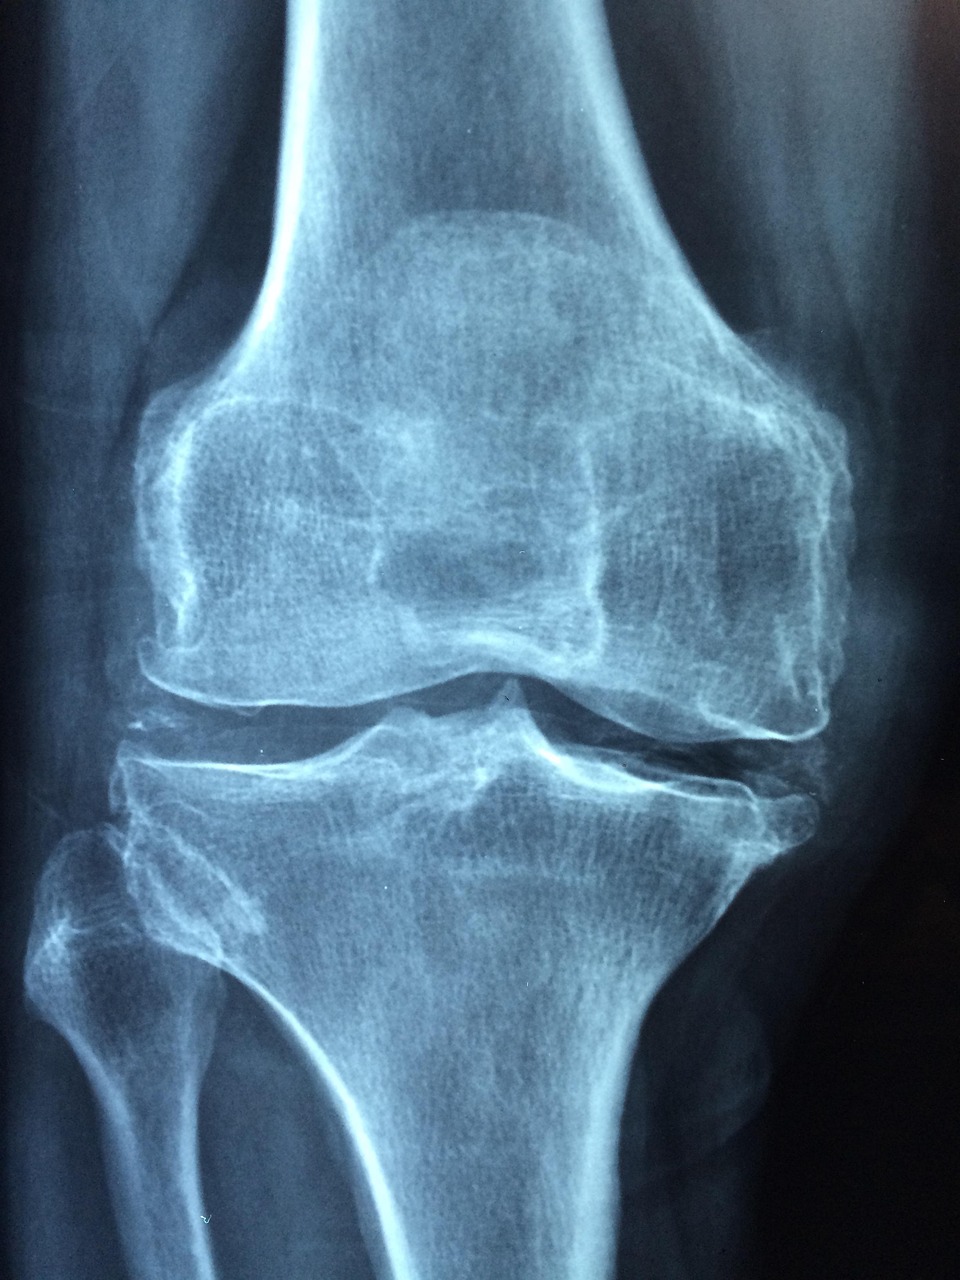

加齢も指関節の変形に大きな影響を与えます。年齢を重ねるにつれて、関節の軟骨が減少し、骨同士の摩擦が増えることで、変形が進行します。特に、更年期はこのプロセスが加速する時期でもあります。

指関節の変形に対する治療法

3. 手術療法

重度の変形が進行した場合、手術が必要になることもあります。手術はリスクも伴いますが、症状が改善されることで生活の質が向上する可能性があります。専門医としっかり相談し、自分に合った治療法を選ぶことが大切です。